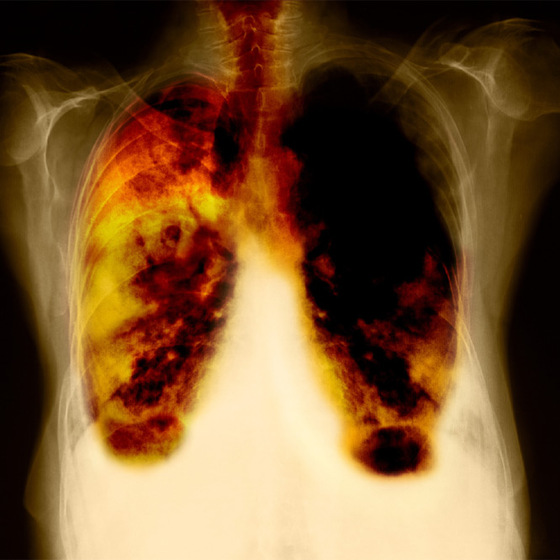

Radiografía de los pulmones de un fumador / GETTY

Prevengamos el cáncer, ¿también el del fumador?

El 95% de los cánceres de pulmón se deben al consumo de tabaco, con lo que la manera más eficaz de evitar la enfermedad consiste en no fumar. En 30 años, las políticas antitabaco españolas han conseguido reducir el número de fumadores mayores de 16 años hasta un 31,5%, según la Encuesta Europea de Salud en España (2009).